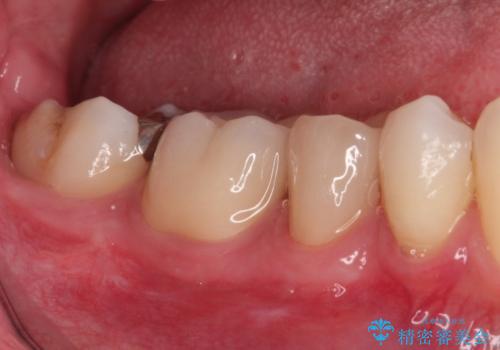

【オールセラミッククラウン】被せ物の治療

- 虫歯の治療を主訴に来院されました。

奥歯は不可逆性歯髄炎の診断のもと、根管治療を行なった後、被せ物の治療を行なっております。

根管治療を行なった歯は被せ物を使用することで、破折しづらくなります。